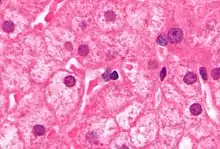

Ground glass hepatocytes as seen in a chronic hepatitis B liver biopsy. H&E stain

PCR tests have been developed to detect and measure the amount of HBV DNA, called the viral load, in clinical specimens. These tests are used to assess a person's infection status and to monitor treatment.[65] Individuals with high viral loads, characteristically have ground glass hepatocytes on biopsy.